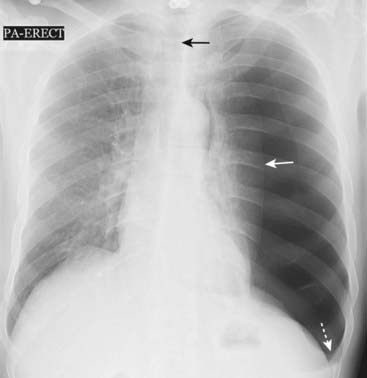

image

Figure 8-10 Large left-sided tension pneumothorax.

Progressive loss of air into the pleural space through a one-way check-valve mechanism may cause a shift of the heart and mediastinal structures away from the side of the pneumothorax and lead to cardiopulmonary compromise by impairing venous return to the heart. In this patient with a spontaneous pneumothorax, the left lung is almost totally collapsed (solid white arrow) and the trachea (solid black arrow) and heart have shifted to the right. The left hemidiaphragm is depressed because of the elevated left intrathoracic pressure (dotted white arrow).